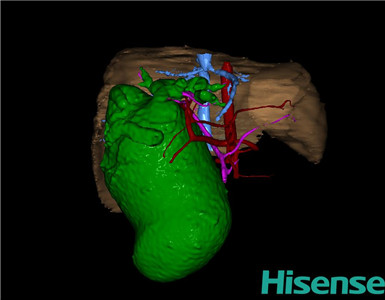

术前三维重建及手术方案设计:

将0.625mm双源薄层CT资料的静脉期和动脉期Dicom格式文件导入海信CAS系统。

通过调节窗宽窗位调整CT序号,对肝实质,胆囊,胆总管,下腔静脉,肝动脉、门静脉及肝静脉等进行三维重建;系统自动计算肝脏体积。

术前手术方案的规划。

术前三维重建:

重建图片